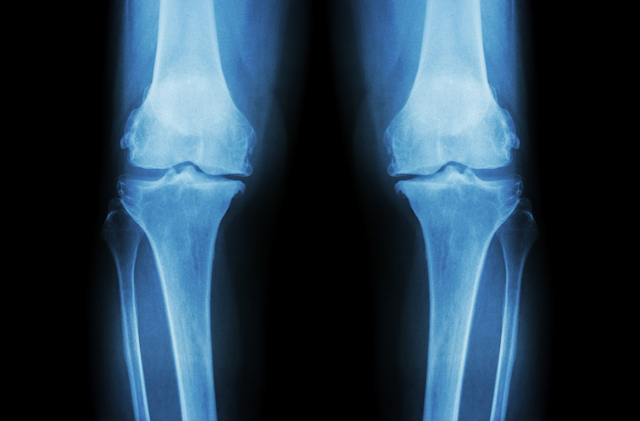

This is an x-ray of knee joints that have osteoarthritis.  Glucosamine sulphate is a supplement to help with pain relief and slow down the progression of osteoarthritis.

Osteoarthritis in both knees showing narrow joint space (joint cartilage loss )and bone spurs. iStock/stockdevil